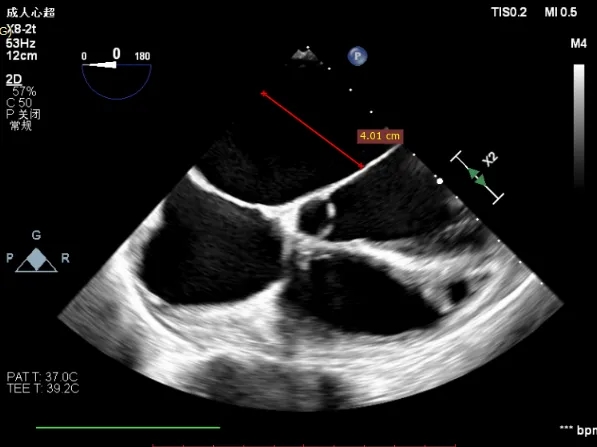

术前Bicom切面

术前X-Plane

术前瓣口面积5.39cm²

后叶长度9.24cm

可用房间隔穿刺高度4.03cm